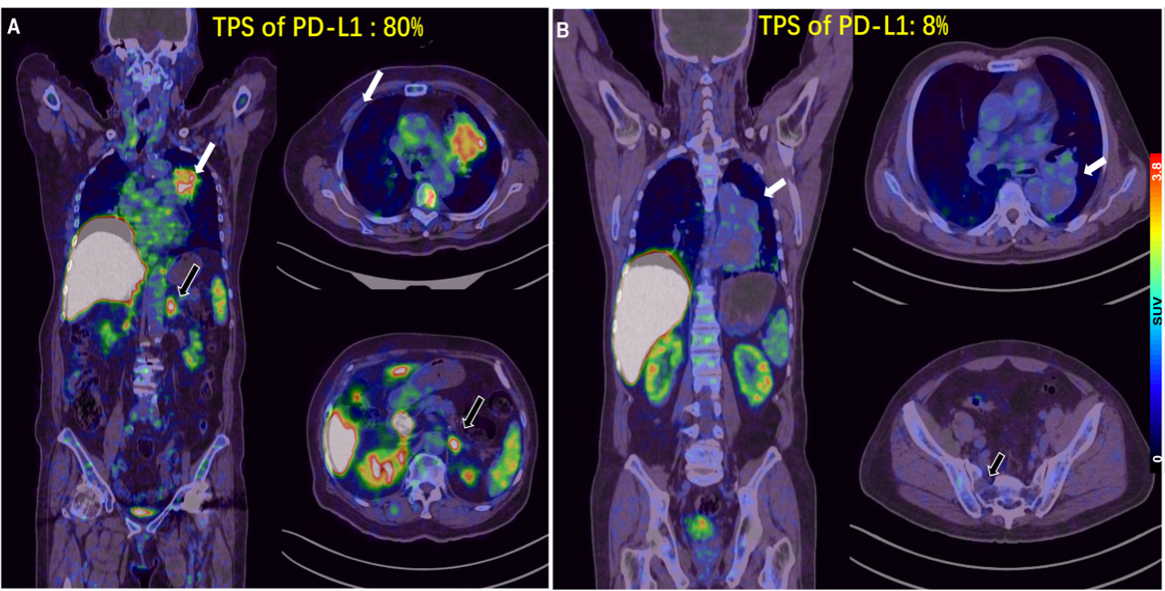

5.目前预测PD-1/PD-L1单抗疗效较为成熟的生物标志物主要是PD-L1表达。北京大学肿瘤医院核医学科和胸部肿瘤内一科合作,研制Ga-68标记的PD-L1靶向低分子量多肽(LMW)探针,首次用于进展期肺癌的临床转化研究展示了在可行的时间窗内用PET显像的方式对患者进行PD-L1表达水平检测的可行性和研究潜力。相关成果以First-in-human evaluation of a PD-L1-binding peptide radiotracer in non-small cell lung cancer patients with PET为题,于 2021年8 月发表在Journal of Nuclear Medicine杂志上。

图5: 68Ga-LMW在不同PD-L1表达水平肿瘤中的PET分析